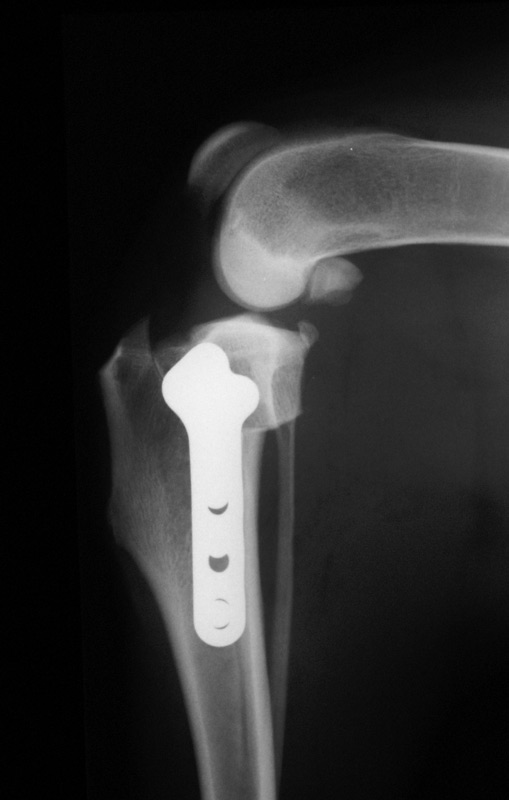

• stabilisation of cruciate ligament failure (TPLO or lateral suture)

(please click on photos to enlarge)